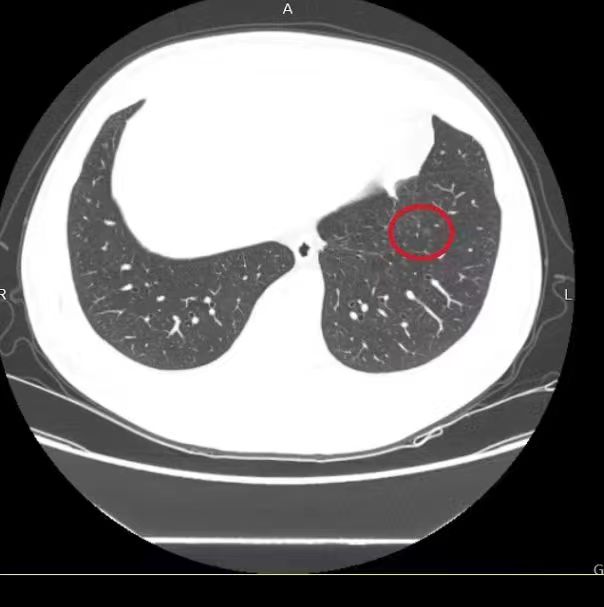

來自杜橋的蔣某半年前體檢發(fā)現(xiàn)肺部多發(fā)結(jié)節(jié),其中最大的肺磨玻璃結(jié)節(jié)6mm。通過醫(yī)院微信公眾號得知我院開設(shè)有肺小結(jié)節(jié)聯(lián)合門診,故至我院就診。經(jīng)過我院浙江省名中醫(yī)李偉林以及呼吸與危重癥科主任張君利、放射科副主任邱敏華的聯(lián)合會診、仔細(xì)研究,認(rèn)為可先中藥治療。根據(jù)患者的中醫(yī)體質(zhì)、肺結(jié)節(jié)的部位大小性狀等制訂出適合該患者的個體化處方。4個月后蔣某復(fù)查胸部CT發(fā)現(xiàn)左下肺的磨玻璃結(jié)節(jié)完全消失,心上的巨石終于落地。